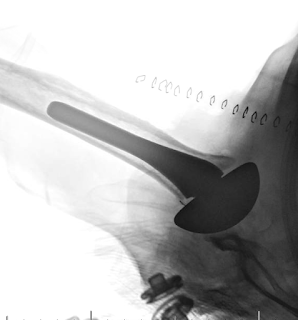

At two weeks after the revision to a thicker polyethylene the shoulder was dislocated anteriorly and interestingly the patient

1. was not aware of when or how this happened

2. had NO PAIN.